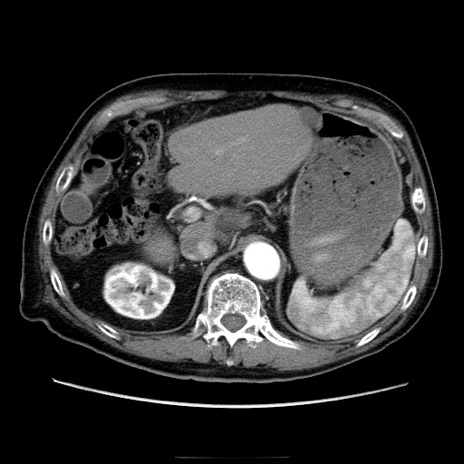

症例21(横断像)

【症例】70歳代男性

【主訴】腹痛

【現病歴】肝硬変・肝細胞癌にてかかりつけの方。約9時間前に食後より腹痛出現。症状が徐々に増悪し、嘔吐出現したため来院。

【既往歴】肝硬変、肝細胞癌(RFA、TACE後)

【身体所見】意識清明、表情苦悶様、BT 36℃、BP 129/78mmHg、P 88bpm、SpO2 97%(RA)、右上腹部から心窩部にかけて圧痛あり、反跳痛なし、筋性防御あり。

【データ】WBC 5800、CRP 0.16